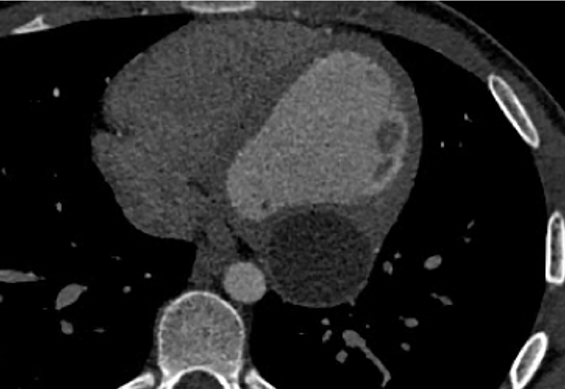

Open cyst during surgery (a). Mycroscopy: Echinococcus hooks and fibrin (b).png)